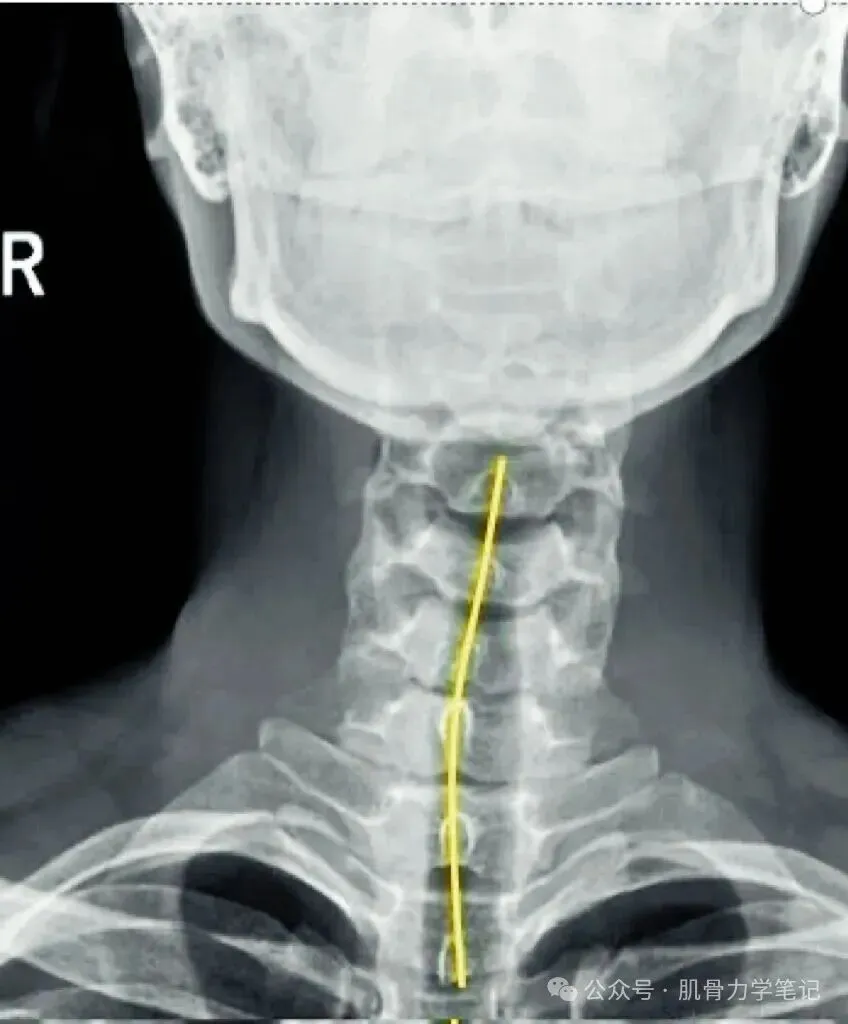

(一)正位片观察要点